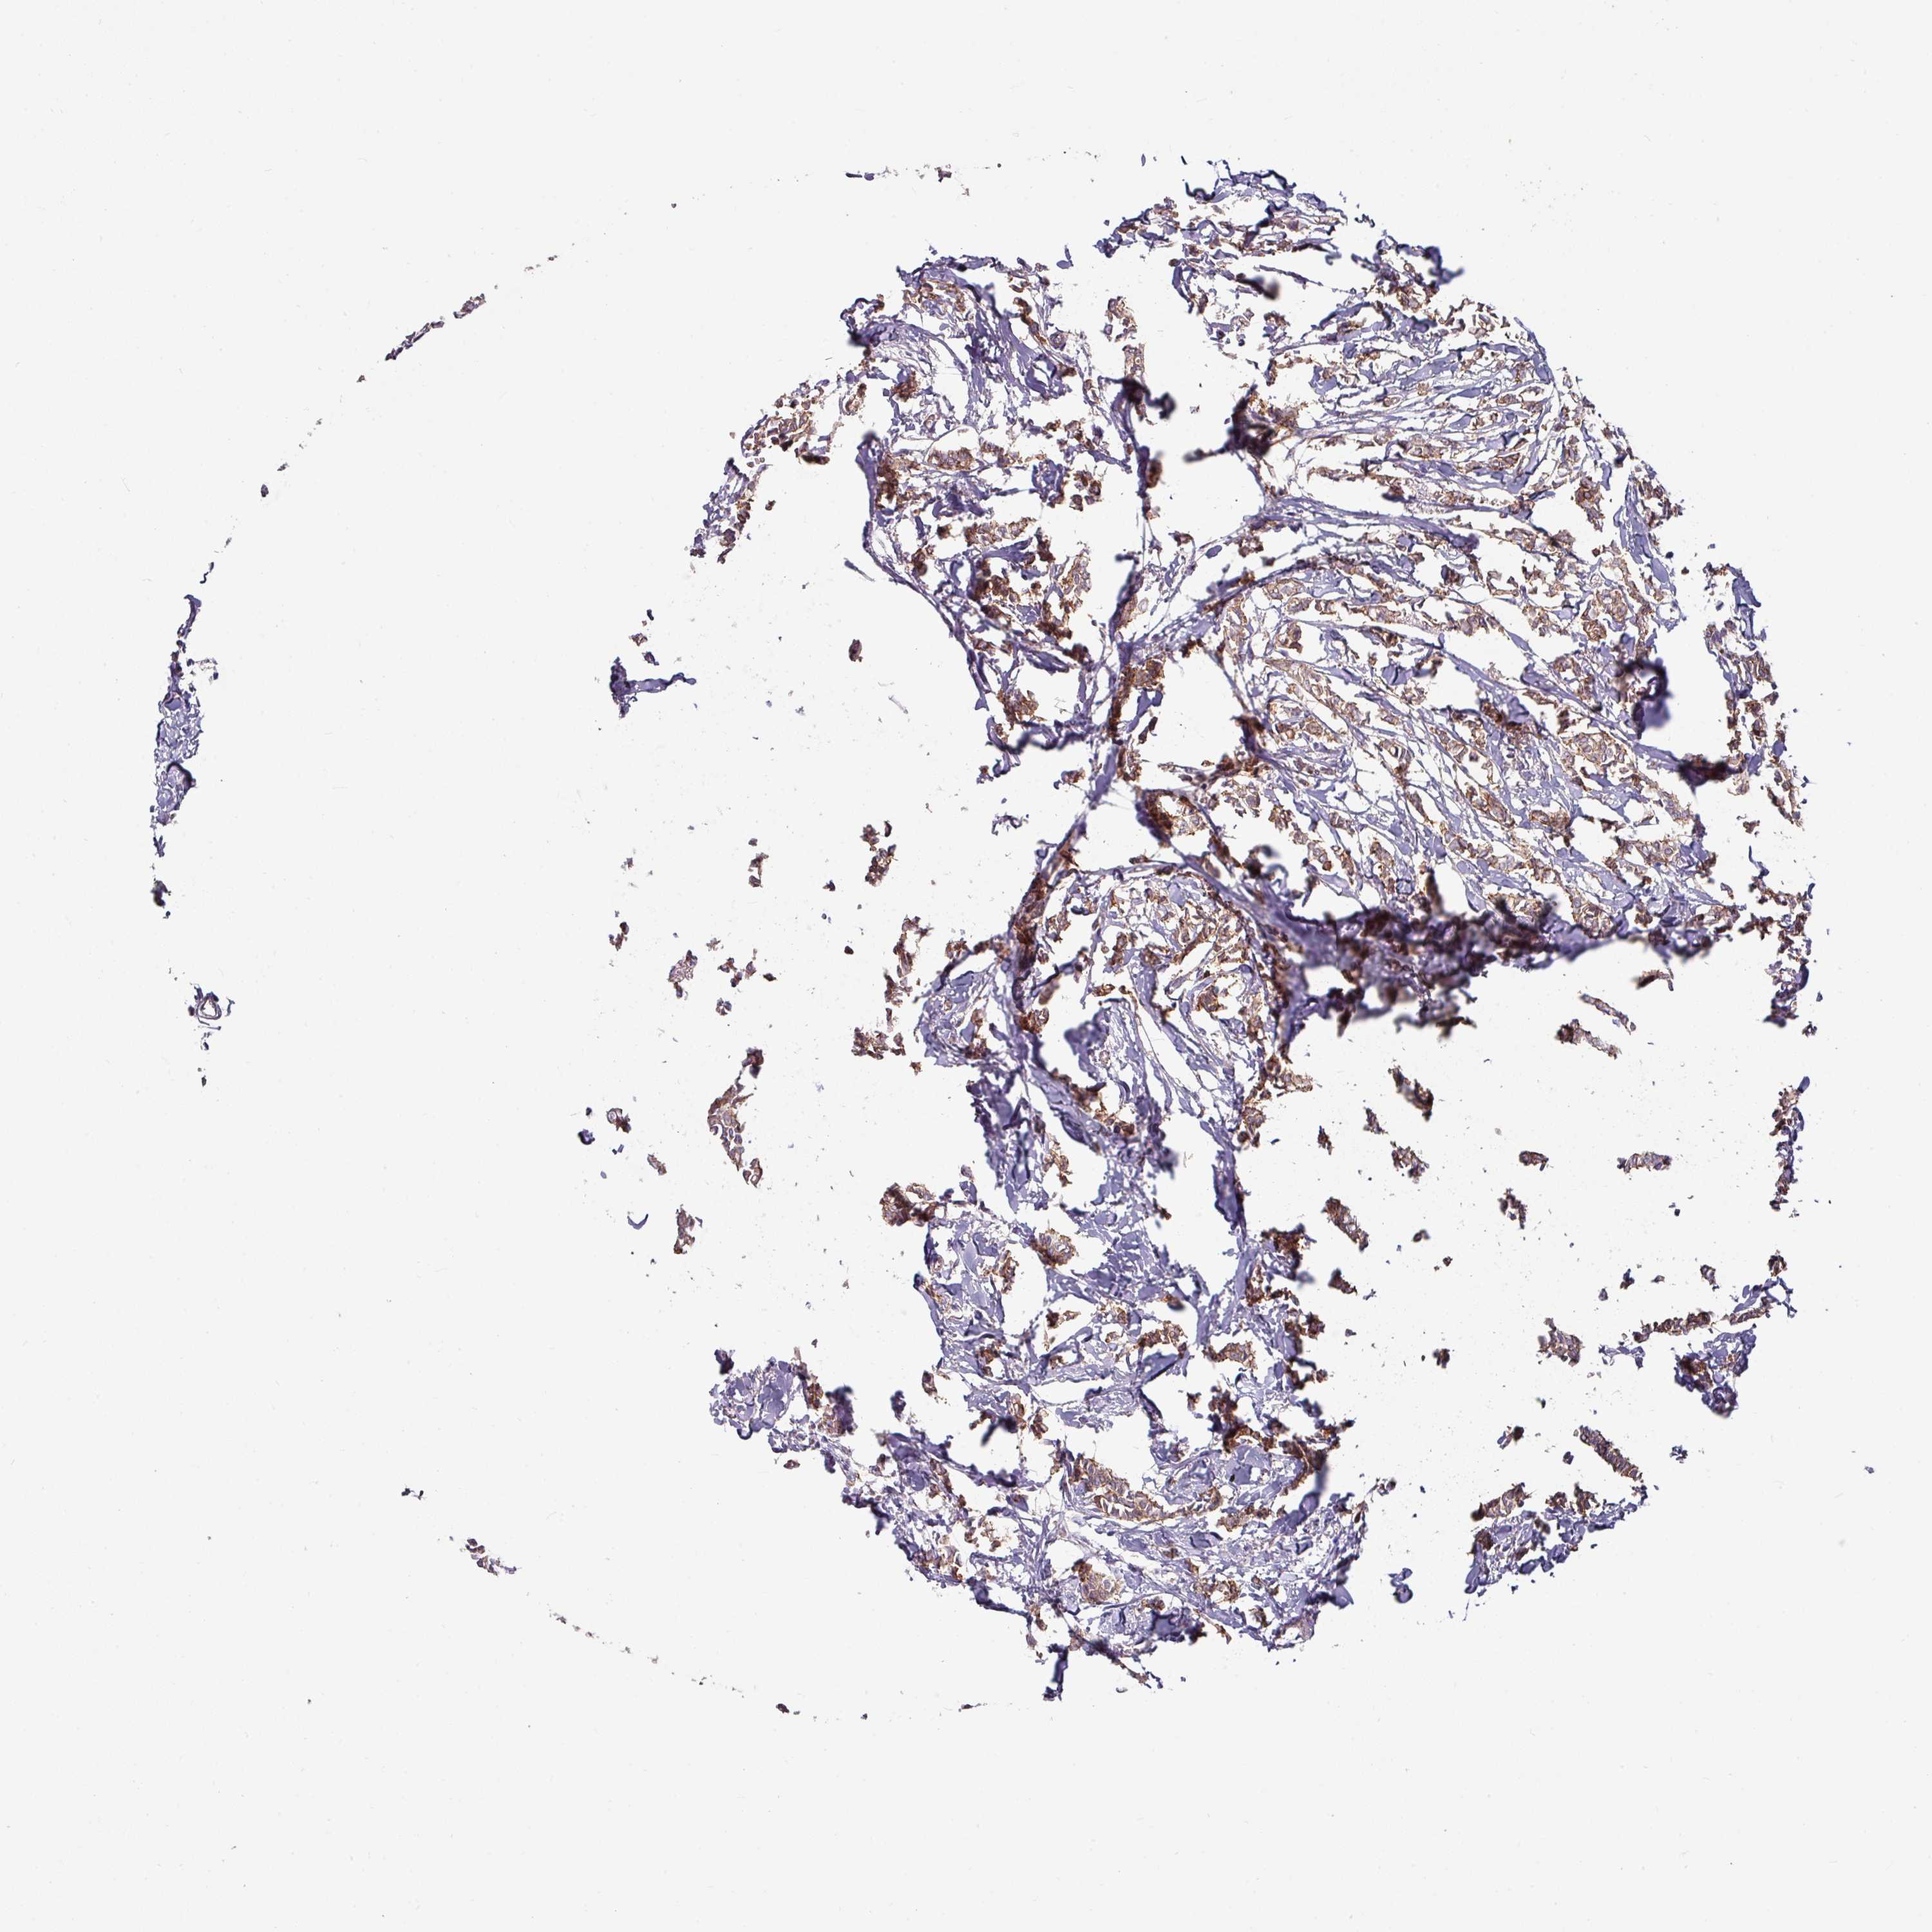

BRCA TCGA BRCA VALIDATION PROTEIN EXPRESSION

ANTIBODIES

AND

VALIDATION